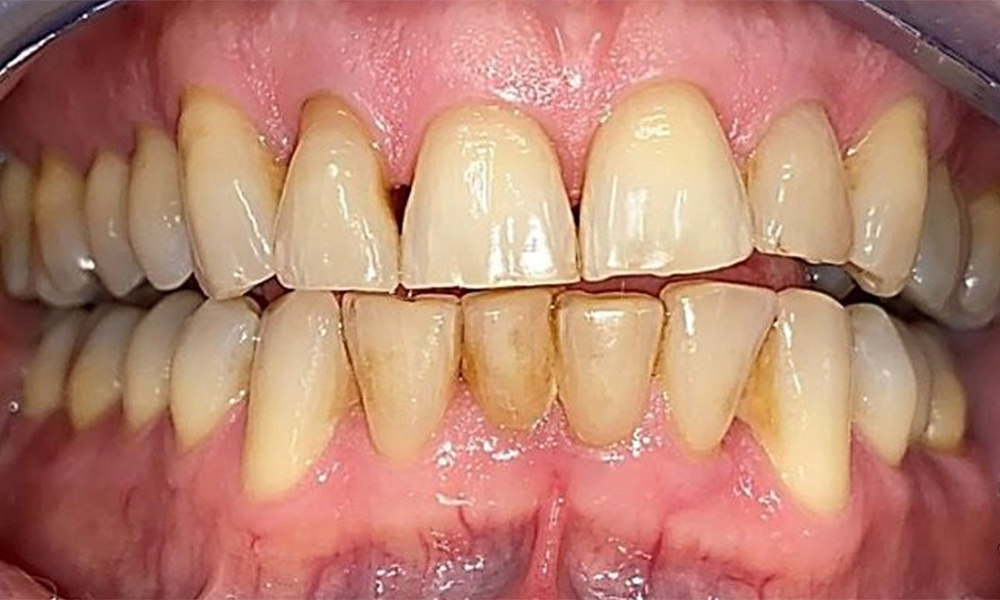

Frontal view with loss of the interdental papillae between 12 and 11.

Fig. 2 Frontal view with loss of the interdental papillae between 12 and 11. © Dr R. Krapf

Right lateral view. Loss of the interdental papillae.

Fig. 3 Right lateral view. Loss of the interdental papillae. © Dr R. Krapf

Left lateral view including the recessions.

Fig. 4 Left lateral view including the recessions. © Dr R. Krapf

The patient has a full dentition with 28 teeth, which includes amalgam and composite fillings in the molar and premolar regions. There is a visible clinical marginal gap present on tooth 14. Tooth 27 has an adequate gold inlay. There are also generalized attritions and abrasions. (Fig. 2, Fig. 3, Fig. 4, Fig. 5, Fig. 6)

The patient has stage II, grade B periodontitis (5). At 1 to 3 mm, the clinical probing depths were within the physiological range. Localized probing depths of 5 mm were observed on the mesiopalatal aspects on both 17 and 27. There are generalized recessions of 1–3 mm with partial loss of the interdental papillae (Fig. 2, Fig. 3, Fig. 4)